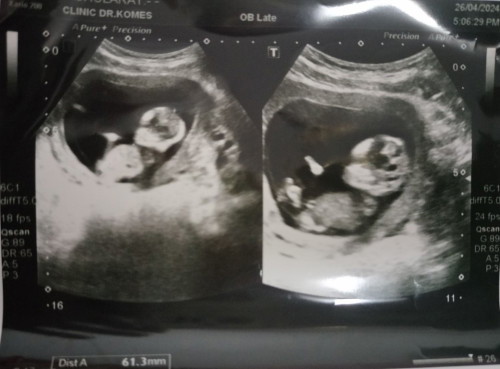

ในภาพคือ 17 วีคแต่ปัจจุบัน36+5วีคคะรอหมอนัด 7 มิ ย.นี้คะ